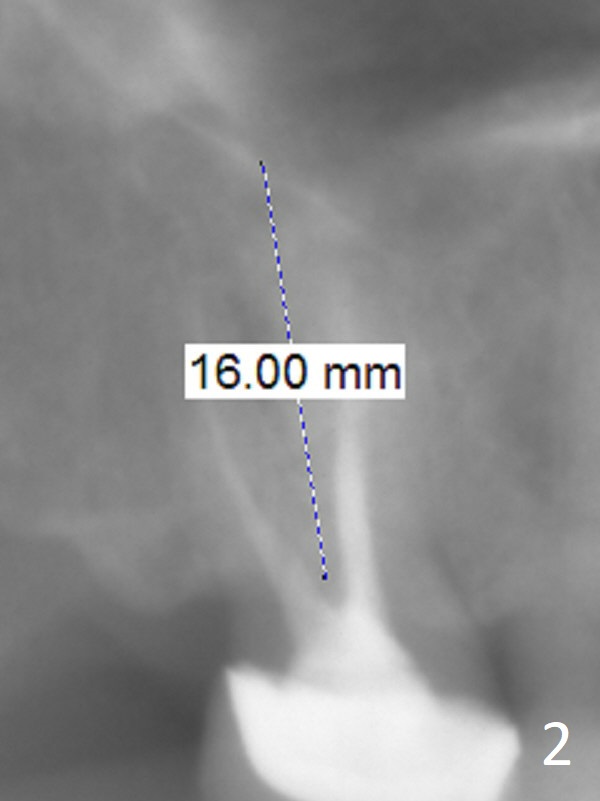

A 58-year-old woman has had RCT done at #2 for several years. The roots are trifurcated with sufficient bone height (Fig.1-3). Recently the tooth becomes symptomatic with formation of a distal fistula (Fig.4). After extraction, the septum (Fig.5 S) may be wide enough for initial drill (Fig.6). If not, resection the thin part of the septum (Fig.7 red line, with small or medium Rongeur) and use the initial drill (Fig.8). Anyway, take PA immediately to avoid sinus membrane perforation. If possible, adopt single drill technique.